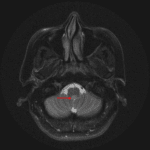

Age: 42

Sex: Female

Indication: Headache

- Intraventricular mass in the inferior aspect of the fourth ventricle measuring 12 x 10 x 10 mm

- No corresponding enhancement or restricted diffusion

- No hydrocephalus

- T2 hyperintense lesion adjacent to the frontal horn of the left lateral ventricle (patient had a history of multiple sclerosis)

- Dilated perivascular space in the right basal ganglia

Subependymoma